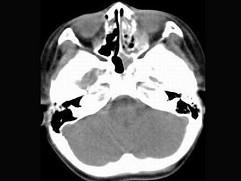

问题 男,7岁,无意发现鼻腔肿物,无明显症状,CT如图所示,最可能诊断为 ( )

选项 A、鼻乳头状瘤 B、鼻炎及副鼻窦粘膜下囊肿 C、鼻炎 D、鼻炎鼻息肉 E、鼻淋巴瘤

答案 D